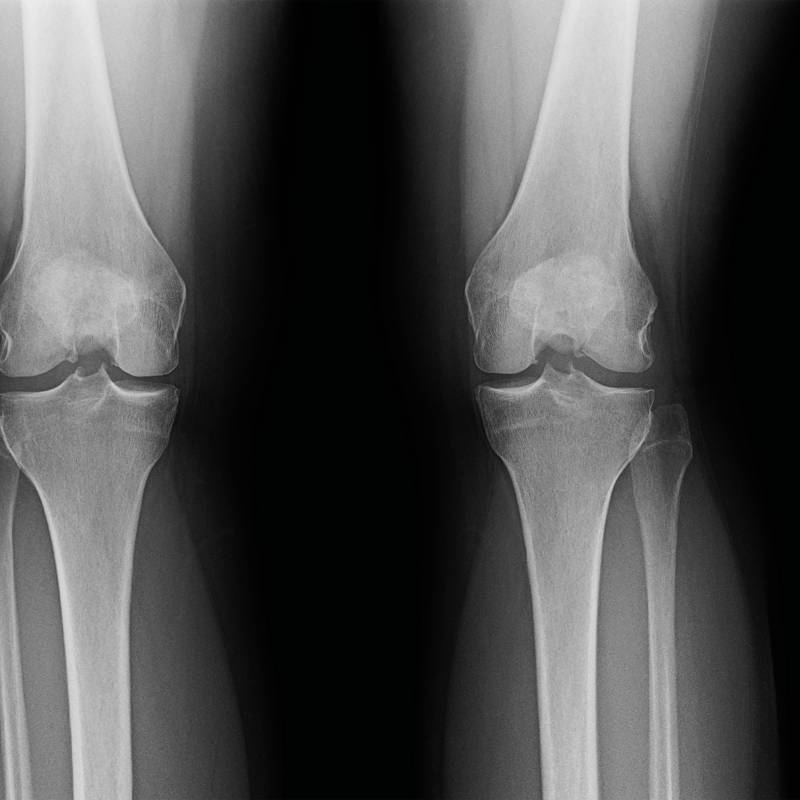

Digunakan untuk mengesan masalah pada sendi lutut.